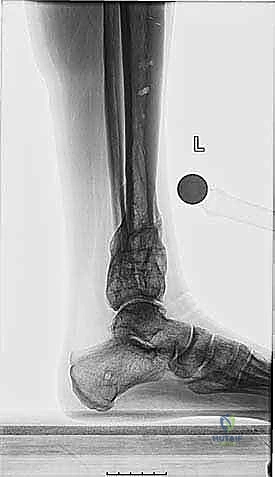

* أشعة سينية طولية للطرفين السفليين أثناء الوقوف (Standing Long-Leg X-rays): هذه هي الصورة الأهم. تسمح للطبيب برؤية محور الساق بالكامل من مفصل الورك، مروراً بالركبة، وصولاً إلى الكاحل.

* الأشعة المقطعية (CT Scan) مع إعادة البناء ثلاثي الأبعاد: ضرورية جداً لتقييم الدوران غير الطبيعي للعظمة (Malrotation) وفهم شكل التشوه في الأبعاد الثلاثة.

* الرنين المغناطيسي (MRI): يُستخدم لتقييم حالة غضاريف مفصل الكاحل، الأربطة، والأوتار المحيطة.